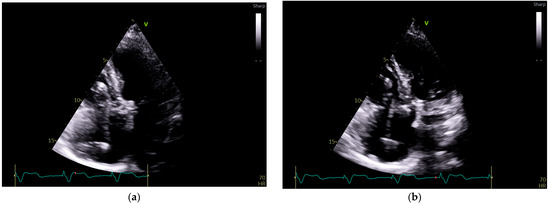

Figure 3.

Echocardiography exam images at admission: A transthoracic echocardiography (TTE) exam was performed in the apical 4-chamber view (a,b) and subcostal view (c,d), revealing the insertion of the pacing probe into the myocardium of the right ventricle free wall, without any visible fractures or ruptures of the lead.